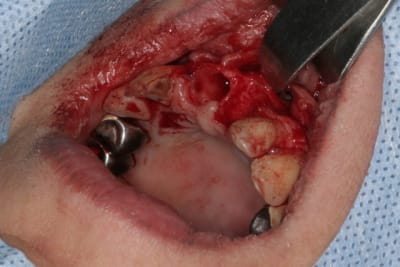

un autre cas EII MCI sur 11/21...mais en photos (j'ai aussi la vidéo, faut que je la passe sur youtube)

Voilà ce que l'on arrive à faire mais ce fut limite!

--

"La seule chose promise d'avance à l'échec, c'est celle que l'on ne tente pas" Paul Emile VICTOR